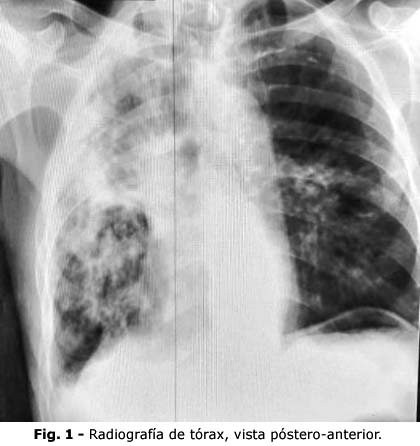

Al final de esta primera fase, el paciente había aumentado 5 kg de peso corporal, las transaminasas y el electrocardiograma estaban inalterados, los esputos BAAR I y II fueron de codificación 2 y tenía mejoría radiológica (Fig. 2).

Conclusiones: La tuberculosis pulmonar puede pasar inadvertida, por ser asintomática o simular una neoplasia pulmonar. La baciloscopía es una herramienta esencial para el diagnóstico diferencial y el tratamiento oportuno, que en este caso produjo mejoría clínico-radiológica y bacteriológica.